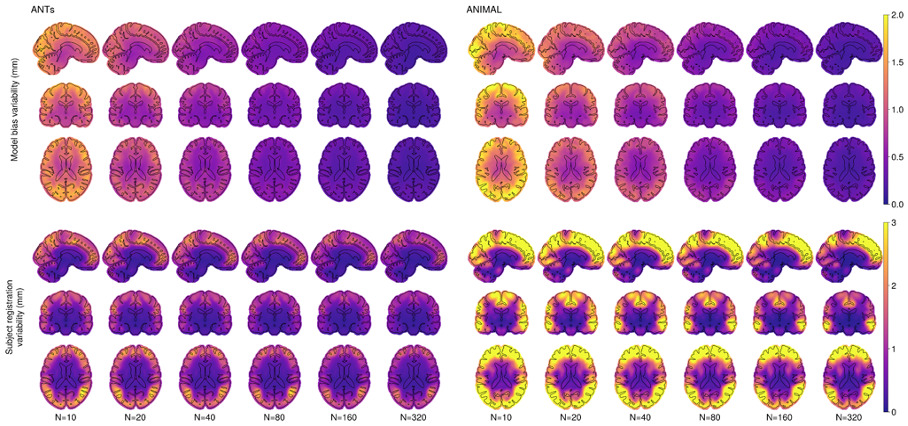

Voxel-level Quantitative Results

Figure 2.1 shows the model bias variability and subject registration variability on the voxel level. As expected, there is higher variability at the cortex compared to the deep brain, which decreases with increasing N. The positional variability (i.e., the mismatch with the N=2000 silver standard depending on the anatomical ROI) is minimized using 80 or 160 subjects when using ANTs. The ANIMAL-based unbiased average requires N=160 to achieve a similar result. Interestingly, individual positional variability (i.e., the anatomical variability between subjects) stays roughly the same for all N of both methods.